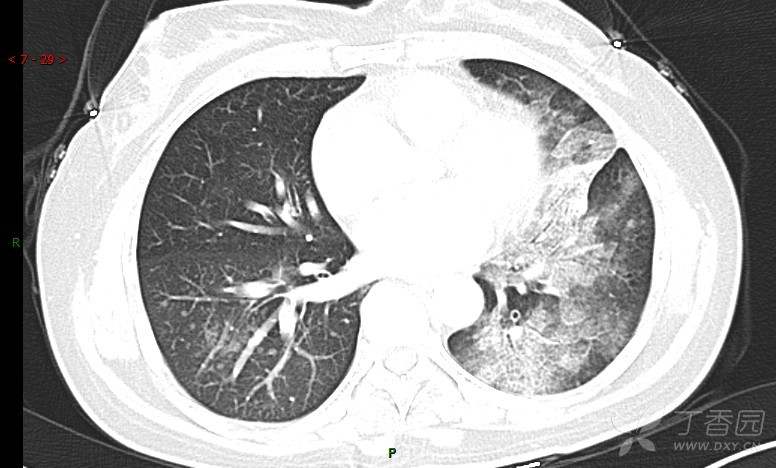

腺泡结节影,蜂窝征,这些都在提示……(病例3连发,附其他2例链接,病理已公布)

咳嗽1年余,加重7天。

患者于1年余前始受凉后出现咳嗽,多为干咳,未在意,未到医院就诊。近3月患者出现咳痰,多为黄色粘痰,量大,伴乏力,偶有头晕、心慌,无发热、胸痛、憋喘,无低热、盗汗、咯血、胸痛,无头痛,无恶心、呕吐、腹痛、腹泻,无尿频、尿急、尿痛,在当地诊所给予抗感染等对症支持治疗(具体药物及剂量不详),症状仍时有反复。患者于1月余前到外院就诊,行胸部CT提示双肺炎症,左肺重,考虑为“间质性肺炎”,给予“左氧氟沙星、利巴韦林、头孢哌酮舒巴坦钠注射液”治疗,复查胸部CT示病灶吸收不理想,后出院继续于诊所对症治疗(具体药物及剂量不详),效果欠佳。7天前患者无明显诱因出现上述症状加重,为求进一步诊治,特来我院就诊,我院门诊以“肺炎(重症)?”收入留观室,留观室给予“盐酸莫西沙星氯化钠”等对症治疗后,今日转入我科。患者自发病以来,神志清,精神差,饮食正常,睡眠增多,大小便正常,体重近3月减轻5公斤余。